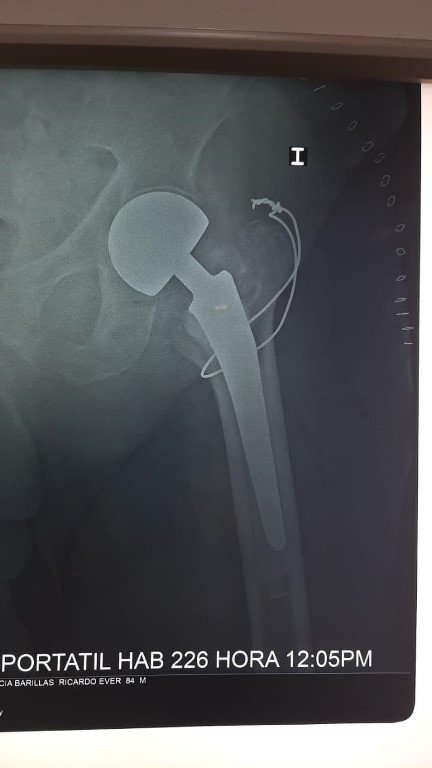

Imágenes de ortopedia y traumatología

Envíado por Dr. José Israel Flores Hernández